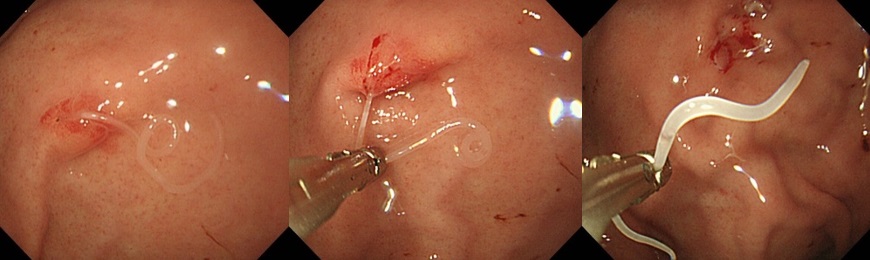

大腸ポリープ切除術、早期癌に対する内視鏡的粘膜剥離術、胃潰瘍などからの出血に対する内視鏡的止血術、食道静脈瘤からの出血に対する結紮術、アニサキス(寄生虫)や薬パッケージの誤飲に対する異物摘出術など。また胆道・膵臓系では、内視鏡を用いた胆石除去や、胆道感染や癌に伴う黄疸に対する内視鏡的な減黄術(ステント留置術)など各種行っております。

『サバ摂取後に寄生したアニサキスの摘出術』